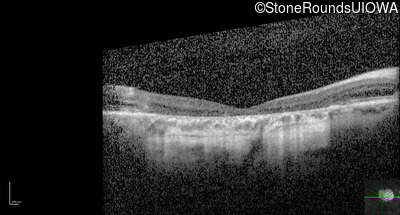

Optical Coherence Tomography - Left - 20/125

Exemplar / OCT Stack